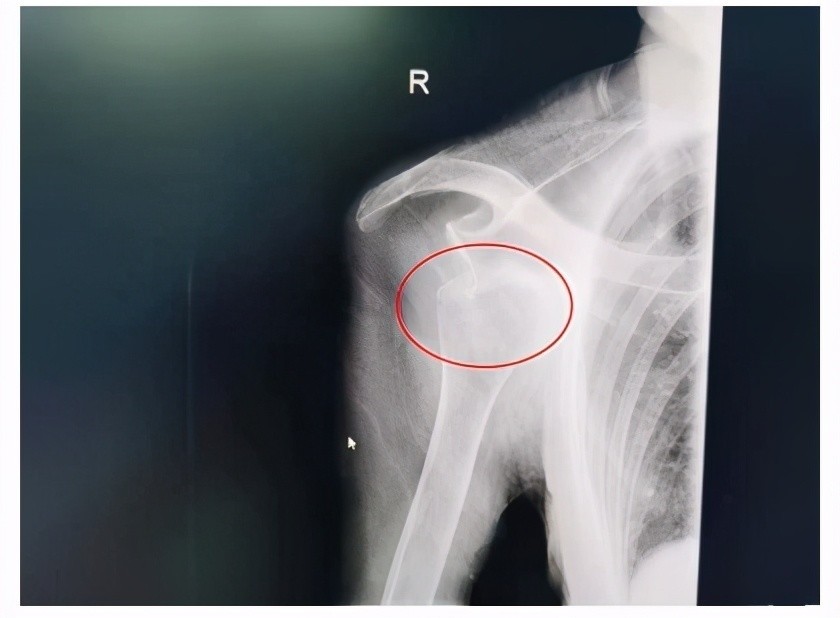

肩关节脱位照片

肩关节脱位照片,

习惯性肩关节脱位

肩关节后脱位的诊断与治疗附典型漏诊病例

肩关节后脱位x线图片